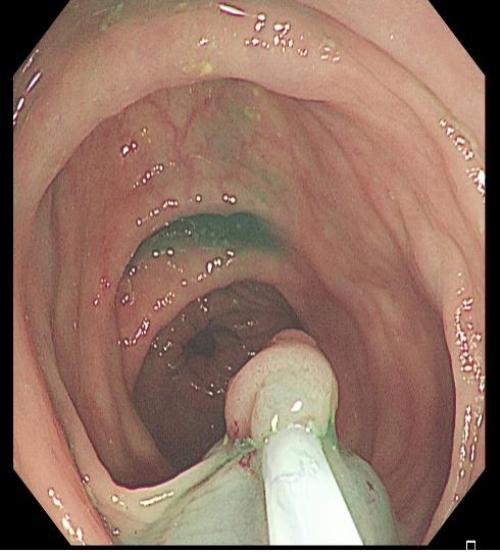

■ Ⅰp 病变

对于大型Ⅰp病变,除以上注意事项外,应采用热圈套方式切除,切除前应于蒂根部充分黏膜下注射(经内镜注射针将2~10 mLl万单位的肾上腺素+亚甲蓝+生理盐水混合液注射于黏膜下,边退针边注射),致使蒂部充分隆起,易于切除(图 3),切除过程中病变应避免接触肠壁,以免形成闭合回路,灼伤肠壁。

上下滑动查看△

图3 Ⅰp 型病变EMR治疗示意图

需要注意的是大型Ⅰp型息肉若蒂部较粗,则可能含粗大滋养血管,切除后极易出血。切除过程中可采用凝-切-凝的方式,减少出血风险。部分较大息肉,可采取分块切除方式,降低操作难度,但此法不利于病理评估。